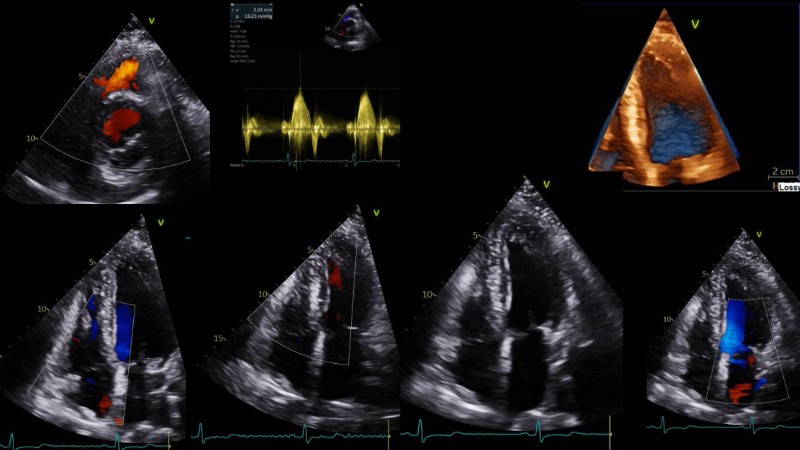

This session explores the evolving landscape of transcatheter aortic valve implantation (TAVI) with a focus on supra-annular valve technology. It covers techniques for achieving commissural alignment, considerations for small aortic annuli, and advantages in treating bicuspid aortic valve disease, supported by clinical data and illustrative cases.